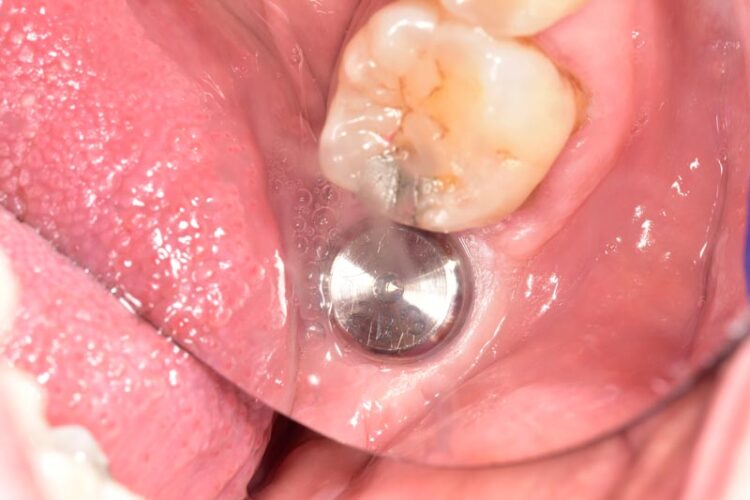

3-D radiographic examination showed sufficient bone available for the placement of a 5.8mm x 9mm BioHorizons Camlog tapered tissue level implant. Surgical placement of this implant involved a two-sided flap and there was no need for hard or soft tissue augmentation. The implant was placed with excellent primary stability and therefore a single-staged approach was followed with a healing abutment being placed at implant placement.

The implant was then left to heal and integrate for three months. No temporary prosthesis was required during this phase.

After three months the healing abutment was then removed. The presence of the healing abutment facilitated the development of an emergence profile from the implant platform during the healing phase. A fixture level impression was taken and a screw-retained crown with the screw emerging in the mid-occlusal area was fabricated. The crown was made on a zirconia framework on a hybrid base abutment layered with e.max ceramic with ultra-polished zirconia subgingivally.